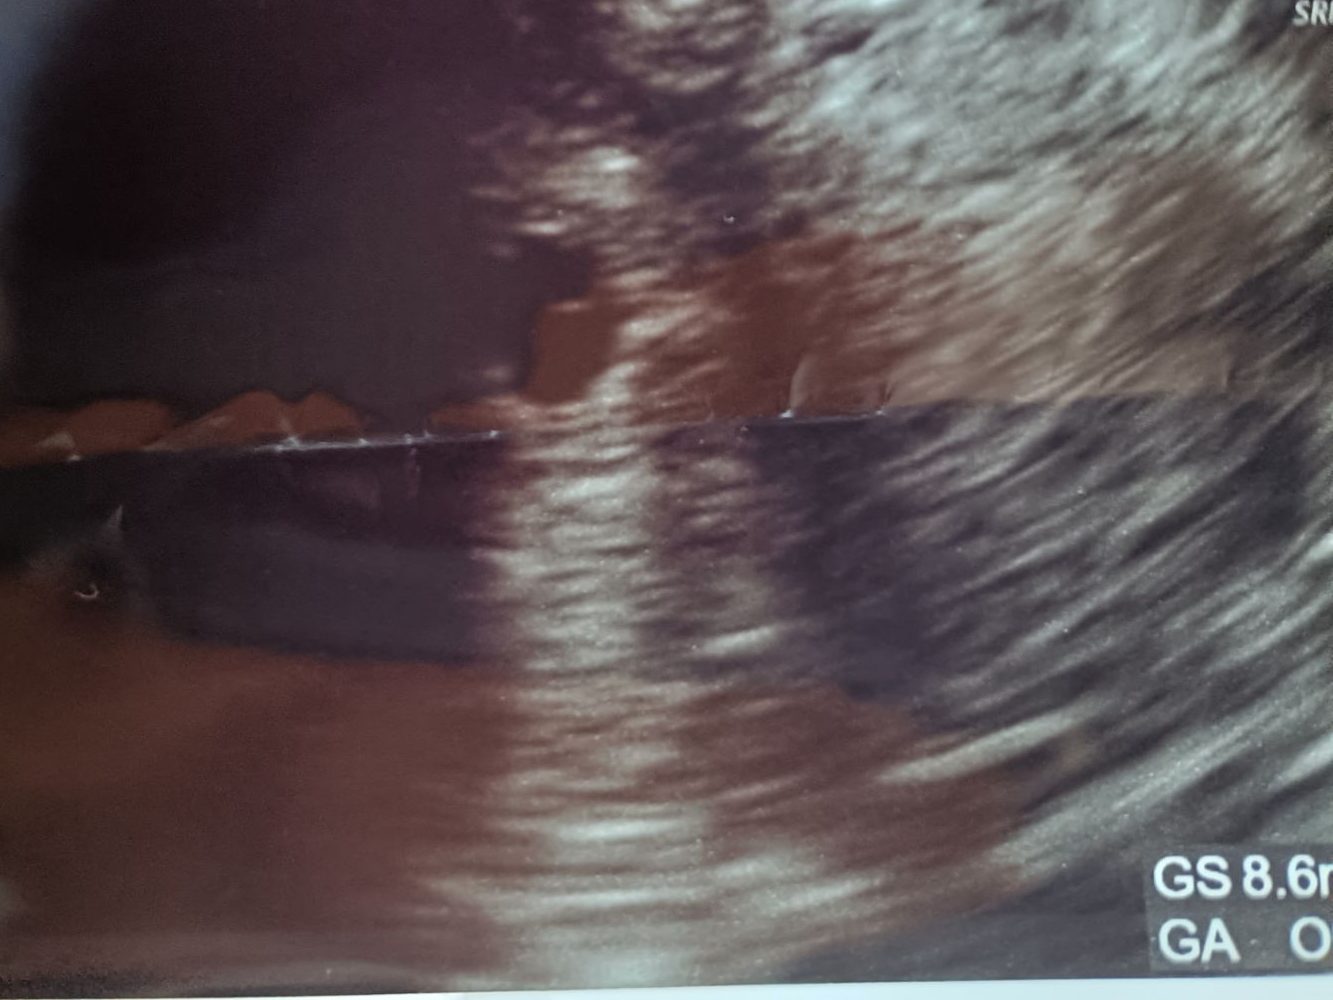

👨⚕️「胎嚢です!この丸いの!」

見えました。確かに黒くて丸いのが!!!

最後に、エコー写真出ます。

苦手な方は見ないでね。